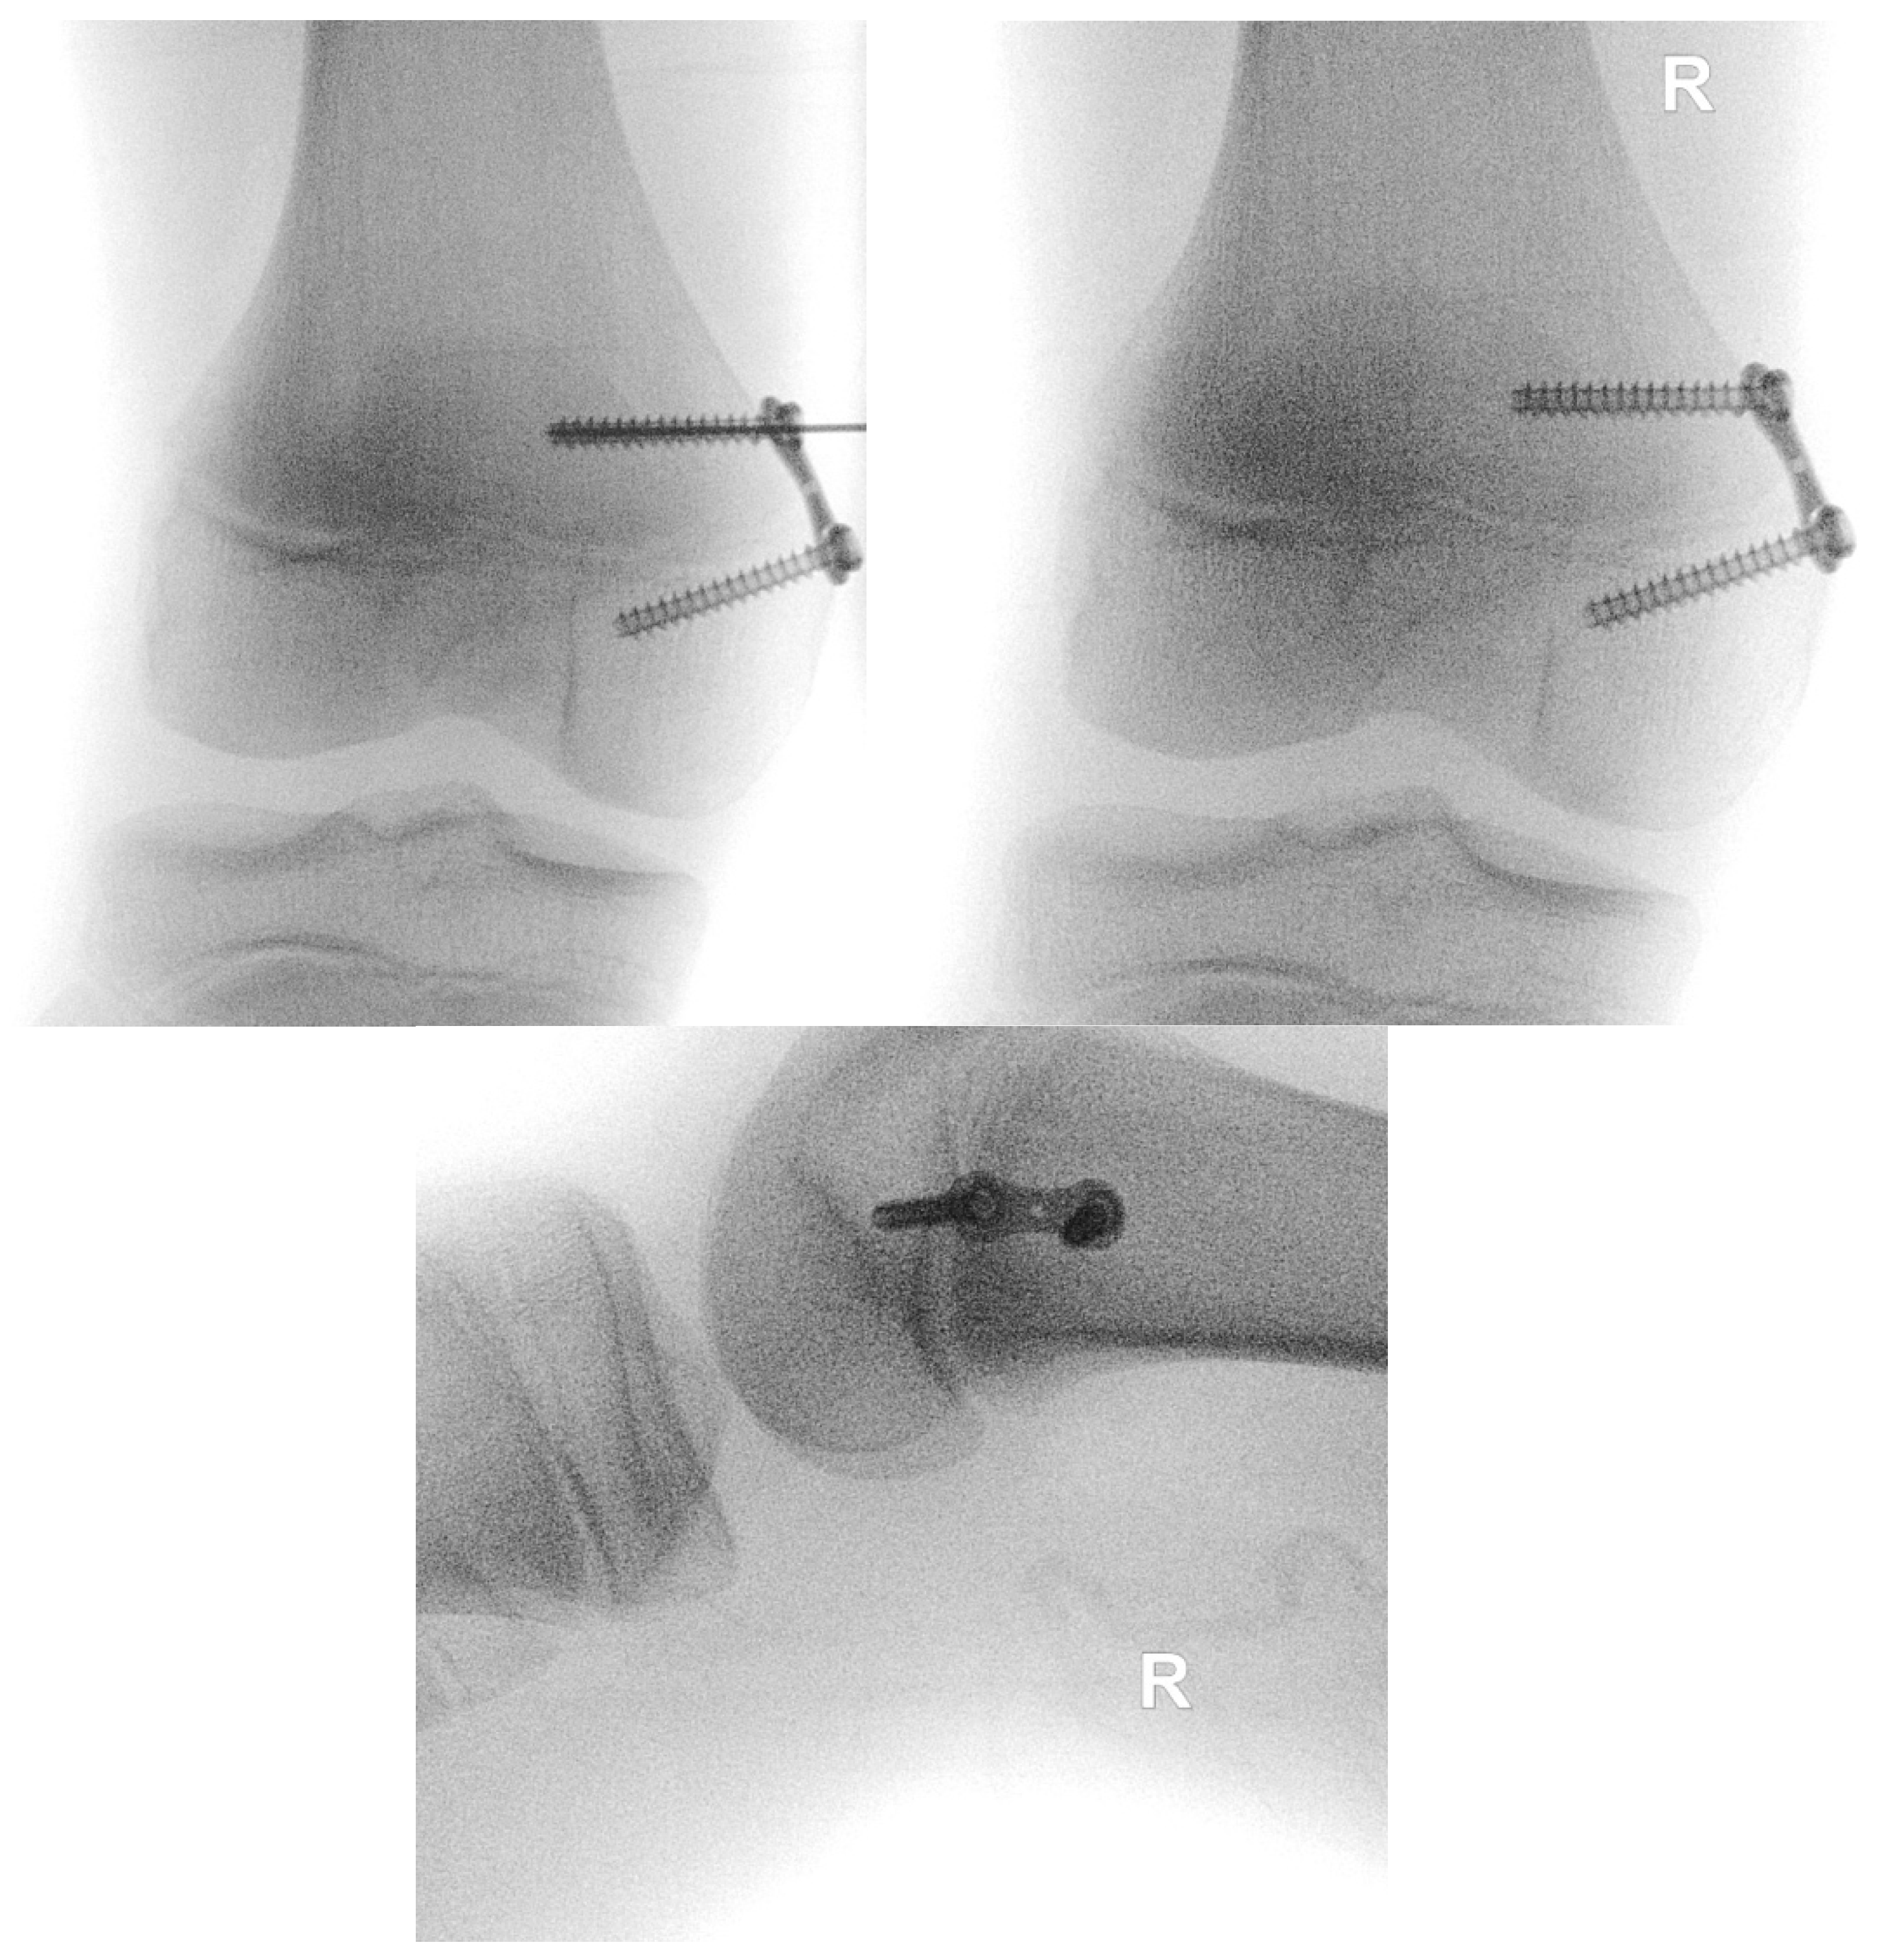

2.2. Surgical Technique